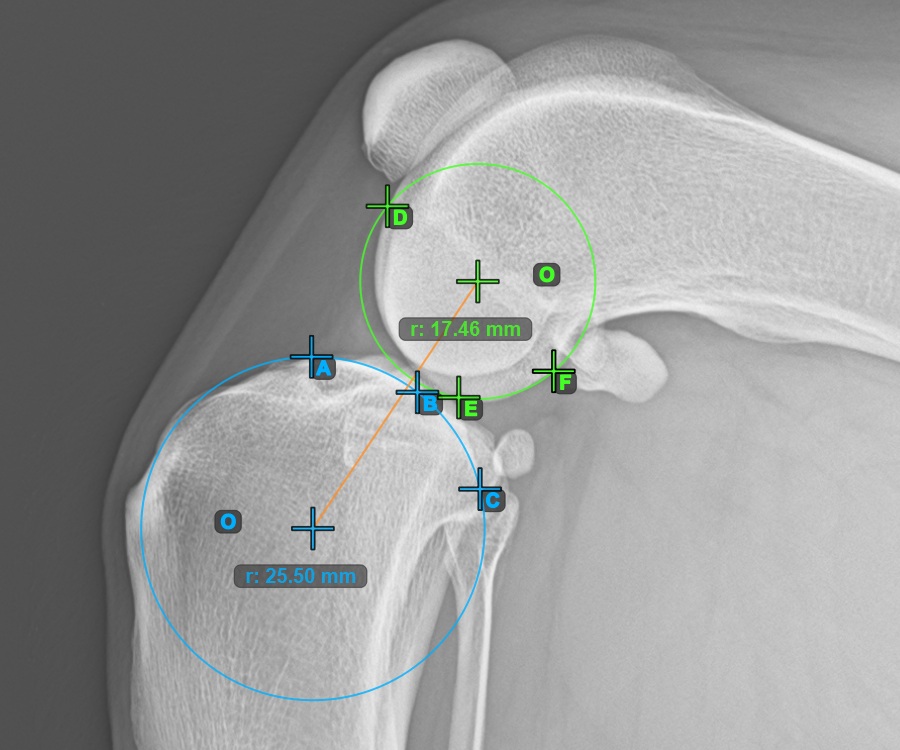

Kezdje el a mérést a három pont megjelölésével a Condylus Medialis Tibialis-on.

Jelölje meg a három pontot a tibia fő condylusán (Medialis Tibialis). A sorrendtől függetlenül ügyeljen arra, hogy megjelölje a legfelső pontot, a legalacsonyabb pontot és a Medialis Tibialis középpontját. A három pont alapján a rendszer automatikusan létrehoz egy kört.

A lenti kép a Condylus Medialis Tibialis-on elhelyezett három pont tipikus elhelyezkedését ábrázolja.